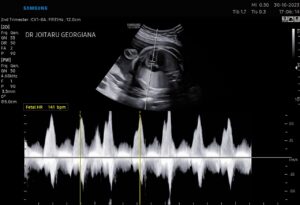

7. NON STRESS TEST sau CARDIOTOCOGRAFIE

Este o explorare simpla si non invaziva a starii de bine a bebelusului intrauterin, prin care se analizeaza bataile inimioarei , tonusul uterin al mamicii si rectia puiutului la miscarile pe care le efectueaza, totul sub atenta monitorizare a mamicii si a echipei medicale.